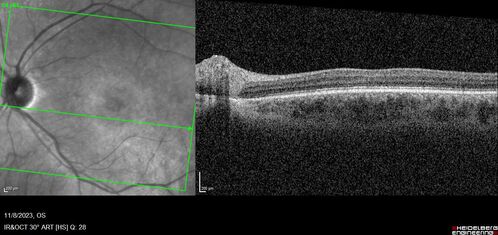

Achromatopsia

28 year old female Good vision since birth started wearing glasses at 2, denies trauma. She does have congenital nystagmus.

VA OD: Dcc20/200-2 PH20/200 NccJ7

VA OS: Dcc20/160 PHNI NccJ7

IOP: TP: OD:15 OS:12